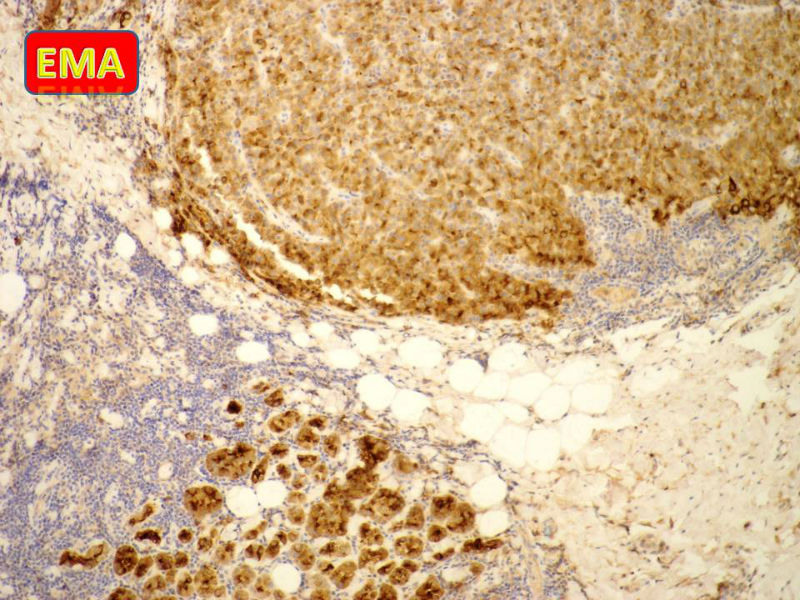

免疫组化